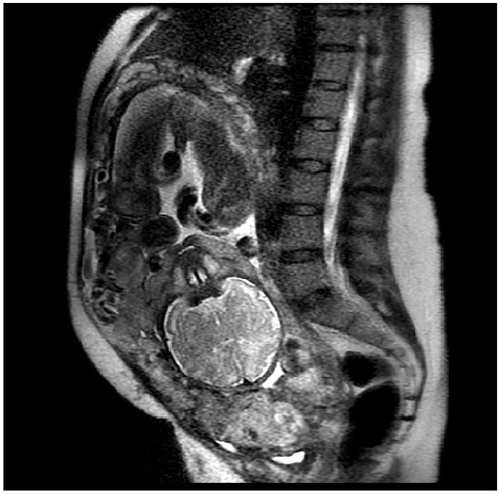

НемедицинаFigure 1. Магнитно-резонансная томография (МРТ) показывает полное предлежание плаценты с очаговым затемнением границы плацента-миометрий по средней линии. Плацентарная ткань соприкасается с куполом мочевого пузыря.